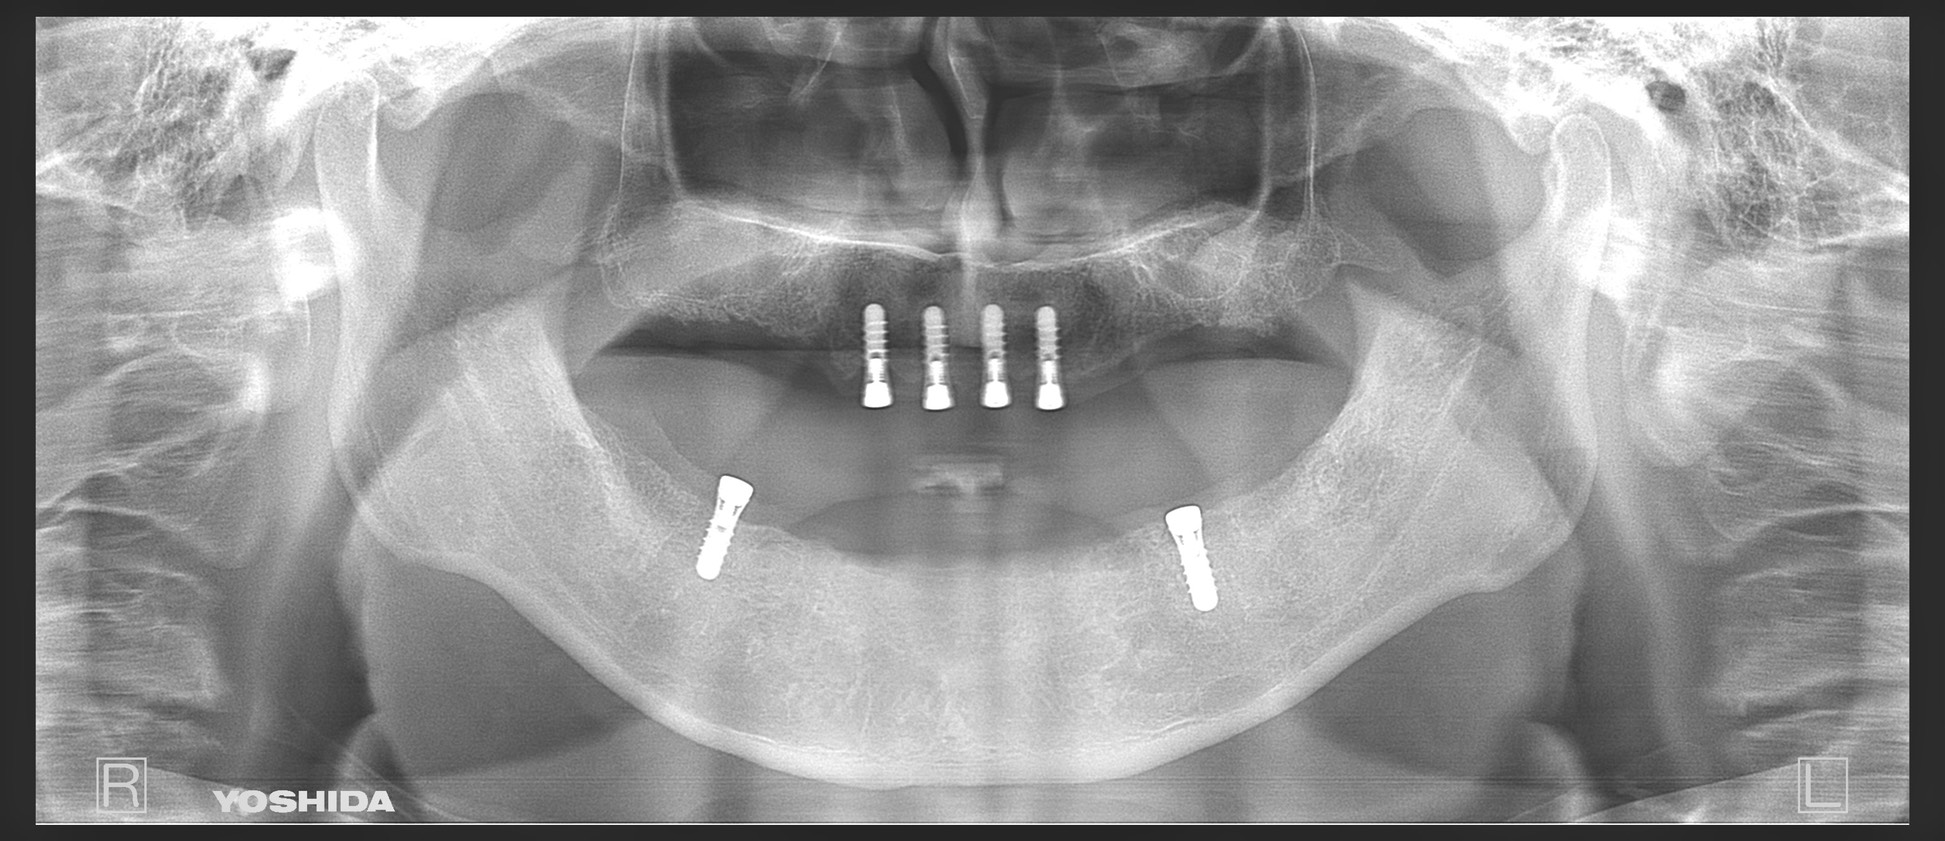

レントゲン写真上でも全顎的に重度の歯周病と診断して、IOD治療を選択されました。

残存歯を抜歯後、上顎は4本、下顎は2本インプラントを埋入しました。